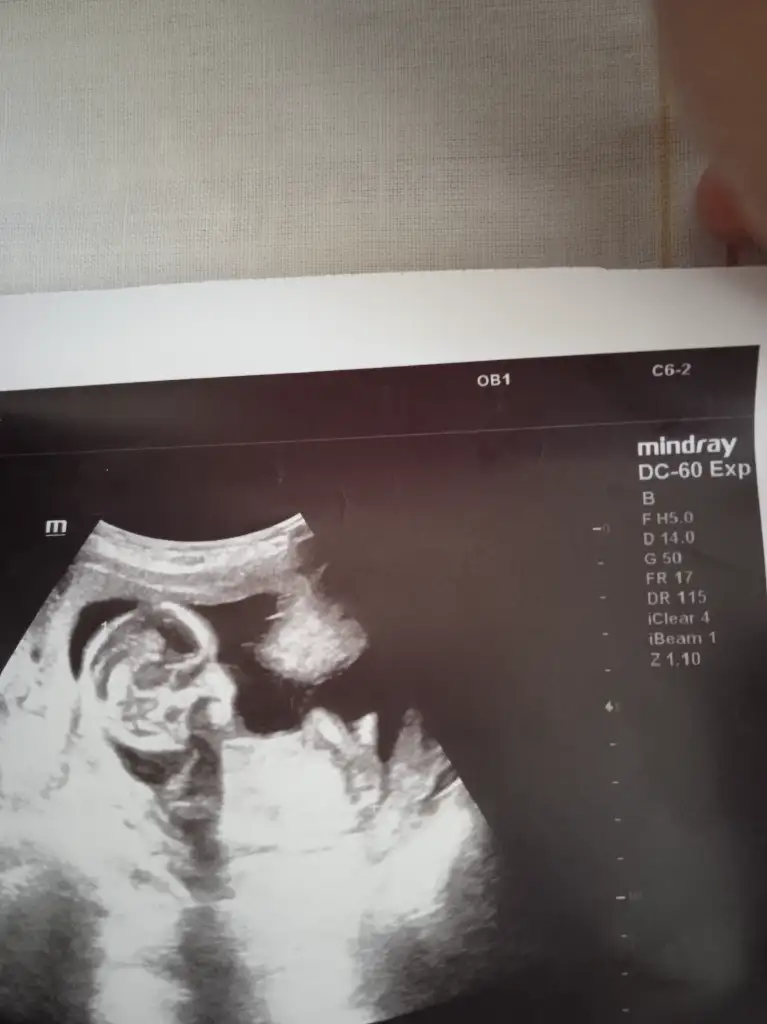

Bunada bakar mısınızErkek gibi

Bacak arasıysa erkek gibiBunada bakar mısınız

Bana da bakar mısınızBacak arasıysa erkek gibi